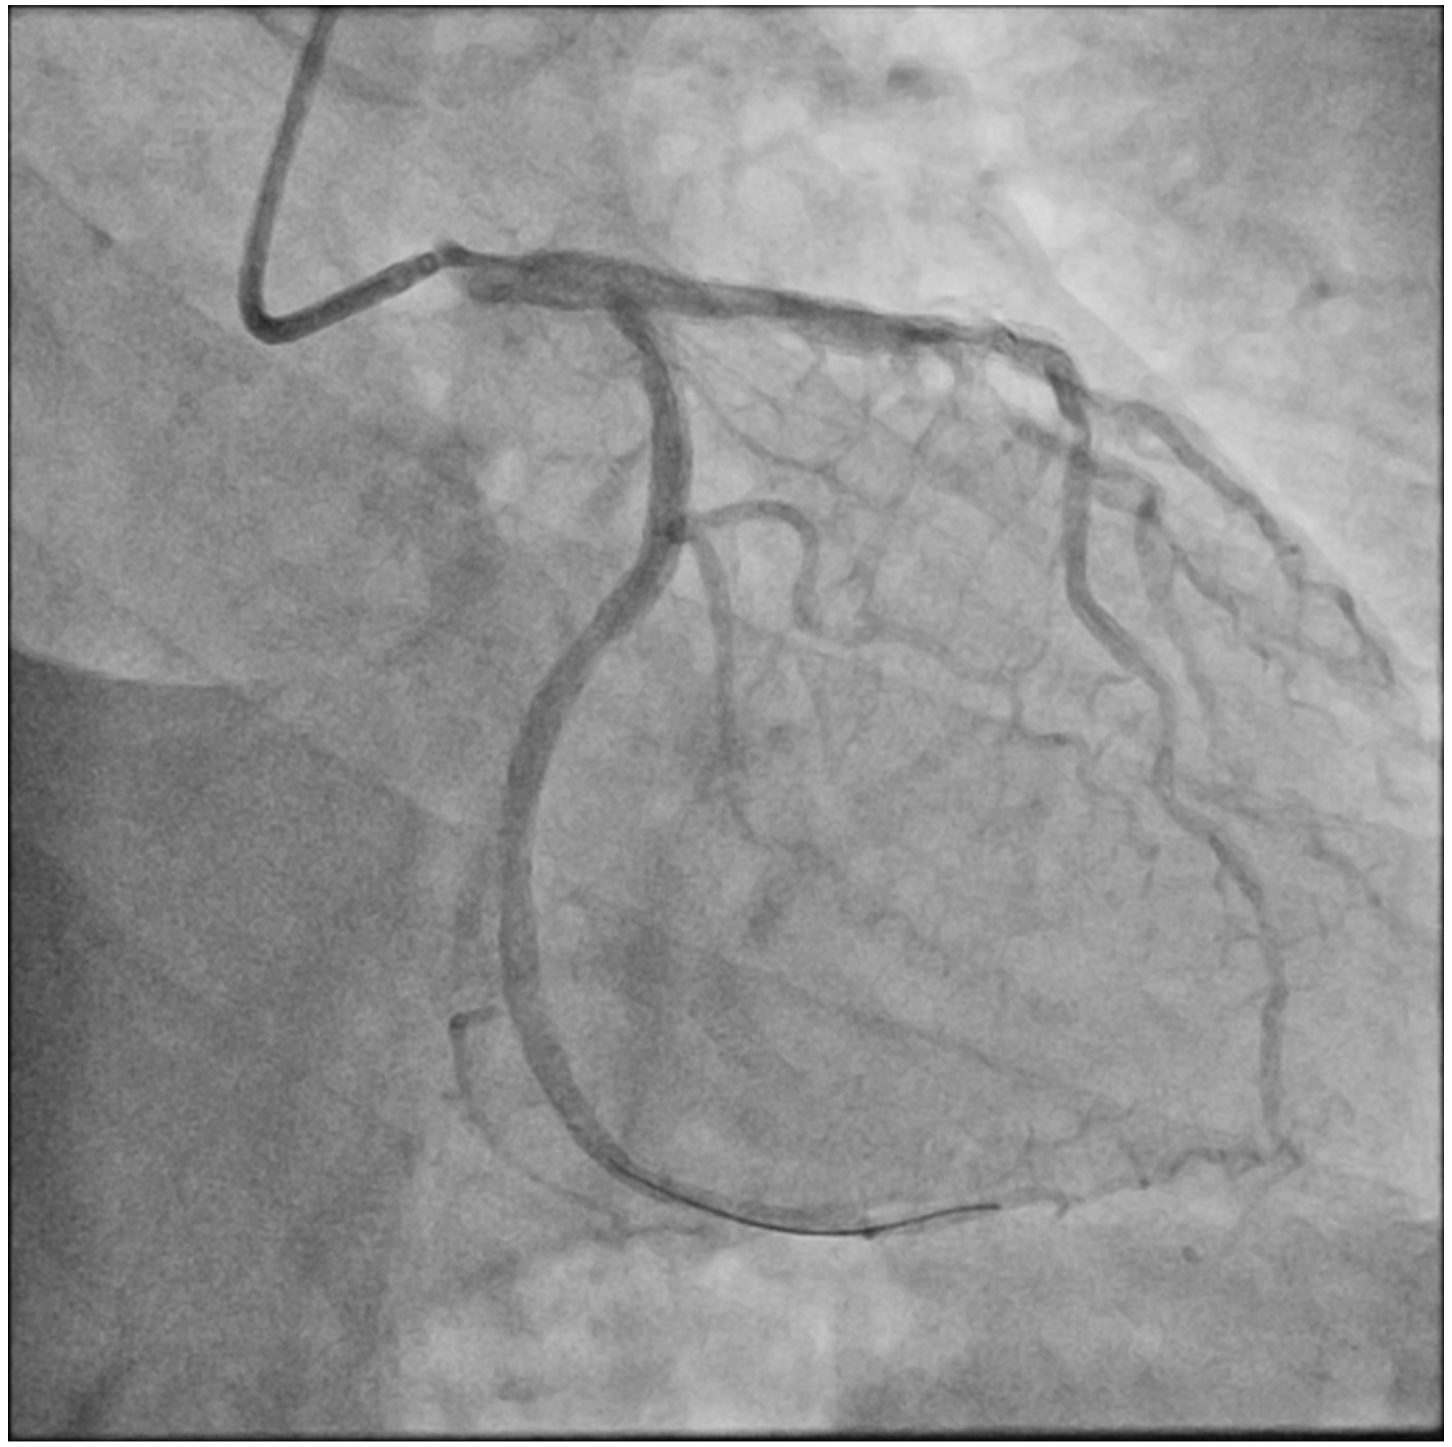

A 71-year-old man who had undergone percutaneous transluminal coronary angioplasty (PTCA) in 2013 was admitted for unstable angina. Coronary angiogram showed 2 de novo lesions at the proximal and distal left circumflex artery (LCX) (Figure 1A). PTCA was performed transradially via a 6-French (Fr) sheath. With a 6-Fr extra-backup 3.5 guide catheter engaging to the left main coronary artery (LM), a 2.5 x 18-mm drug-eluting stent (DES) was delivered to the distal LCX lesion but was inadequate for complete lesion coverage (Figure 1B). During retrieval, the stent was found dislodged at the distal LM bifurcation (Figure 1C).

Distal small balloon retrieval was unsuccessful (Figure 1D). With the help of the Balloon-Assisted Guide-extension (BAG) system, the stent could be optimally positioned at the proximal LCX lesion by forward pushing with a 6-Fr Guideliner V3 catheter (Teleflex) and backward pulling by the small balloon (Figure 1E and F; Video). It was then deployed by sequential balloon dilatation with good expansion (Figure 1G and H). Another 2.5 x 24-mm DES was deployed at the distal LCX, which gave an excellent final angiographic result (Figure 1I and J).